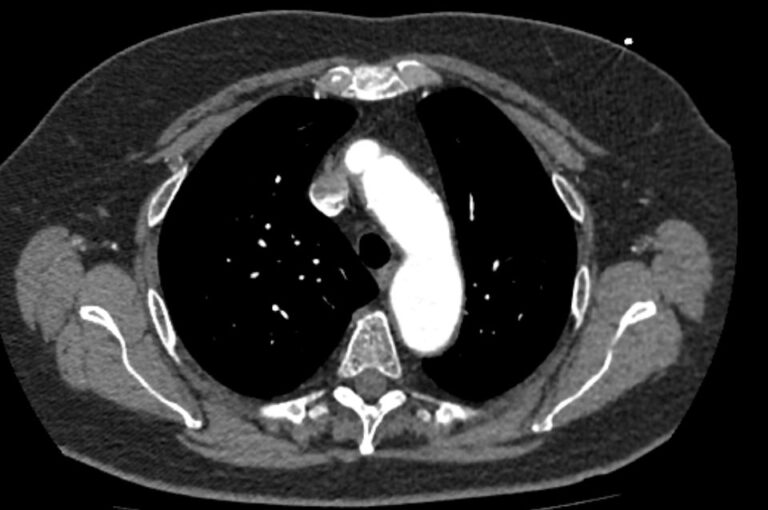

Грудная аорта делится на несколько отделов – восходящий отдел аорты, дуга аорты и нисходящий отдел. Корень аорты отходит непосредственно от левого желудочка, в его состав входят синусы Вальсальвы от которых берут начало коронарные артерии. После корня, прослеживается тубулярная часть восходящего отдела аорты, которая переходит в дугу аорты.

Дуга аорты дает начало брахиоцефальным артериям, которые питают головной мозг и верхние конечности. Затем следует нисходящий отдел аорты, распространяющийся через отверстие в диафрагме. От грудного отдела аорты отходят висцеральные артерии, кровоснабжающие органы средостения: бронхиальные, пищеводные, перикардиальные, медиастинальные артерии.

Одним из информативных методов диагностики сосудистой патологии является мультиспиральная компьютерная томография грудной аорты и ее ветвей (КТ-ангиография). Метод сканирования при помощи рентгеновских лучей и цифровой обработки данных позволяет получать послойные снимки сосудов и трехмерные реконструкции сосудистой системы в мельчайших подробностях.

Для того, чтобы качественно визуализировать сосудистую систему КТ-ангиография предусматривает в обязательном порядке применение контрастного усиления. Йодсодержащее контрастное вещество вводится пациенту внутривенно и, благодаря способности контраста поглощать рентгеновские лучи, ярко контрастирует сосудистую систему на фоне окружающих тканей.

КТ-ангиография позволяет диагностировать аневризмы аорты, сосудистые аномалии развития, воспалительные изменения стенок сосудов, пристеночные тромбы, сужения просвета сосудов за счет сдавления извне близлежащими опухолевыми образованиями.